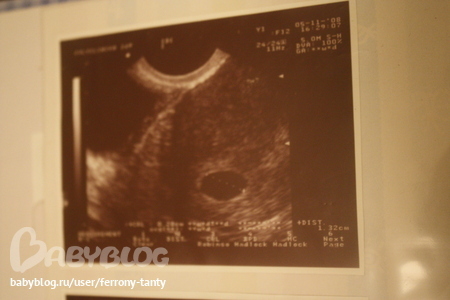

Больше вот это похоже на плодное яйцо, но у тебя матка должна быть не в норме при беременности, а увеличена и эндометрий тоже и желтое тело должно визуализироваться, если всего этого нет в заключении, то лучше сильно не обнадеживай себя, а то потом расстроишься.

Дорогая, не хочу тебя огорчать, но скорее всего нет. такая точка бывает на 3-4 неделе. на твоём "сроке" (3 ноября) уже всёё очень видно. бывают конечно исключения. смотри, вот тут у меня узи 5 недель.

А мне всегда казалось, что Б - это черное пятнышко с белой точкой внутри........